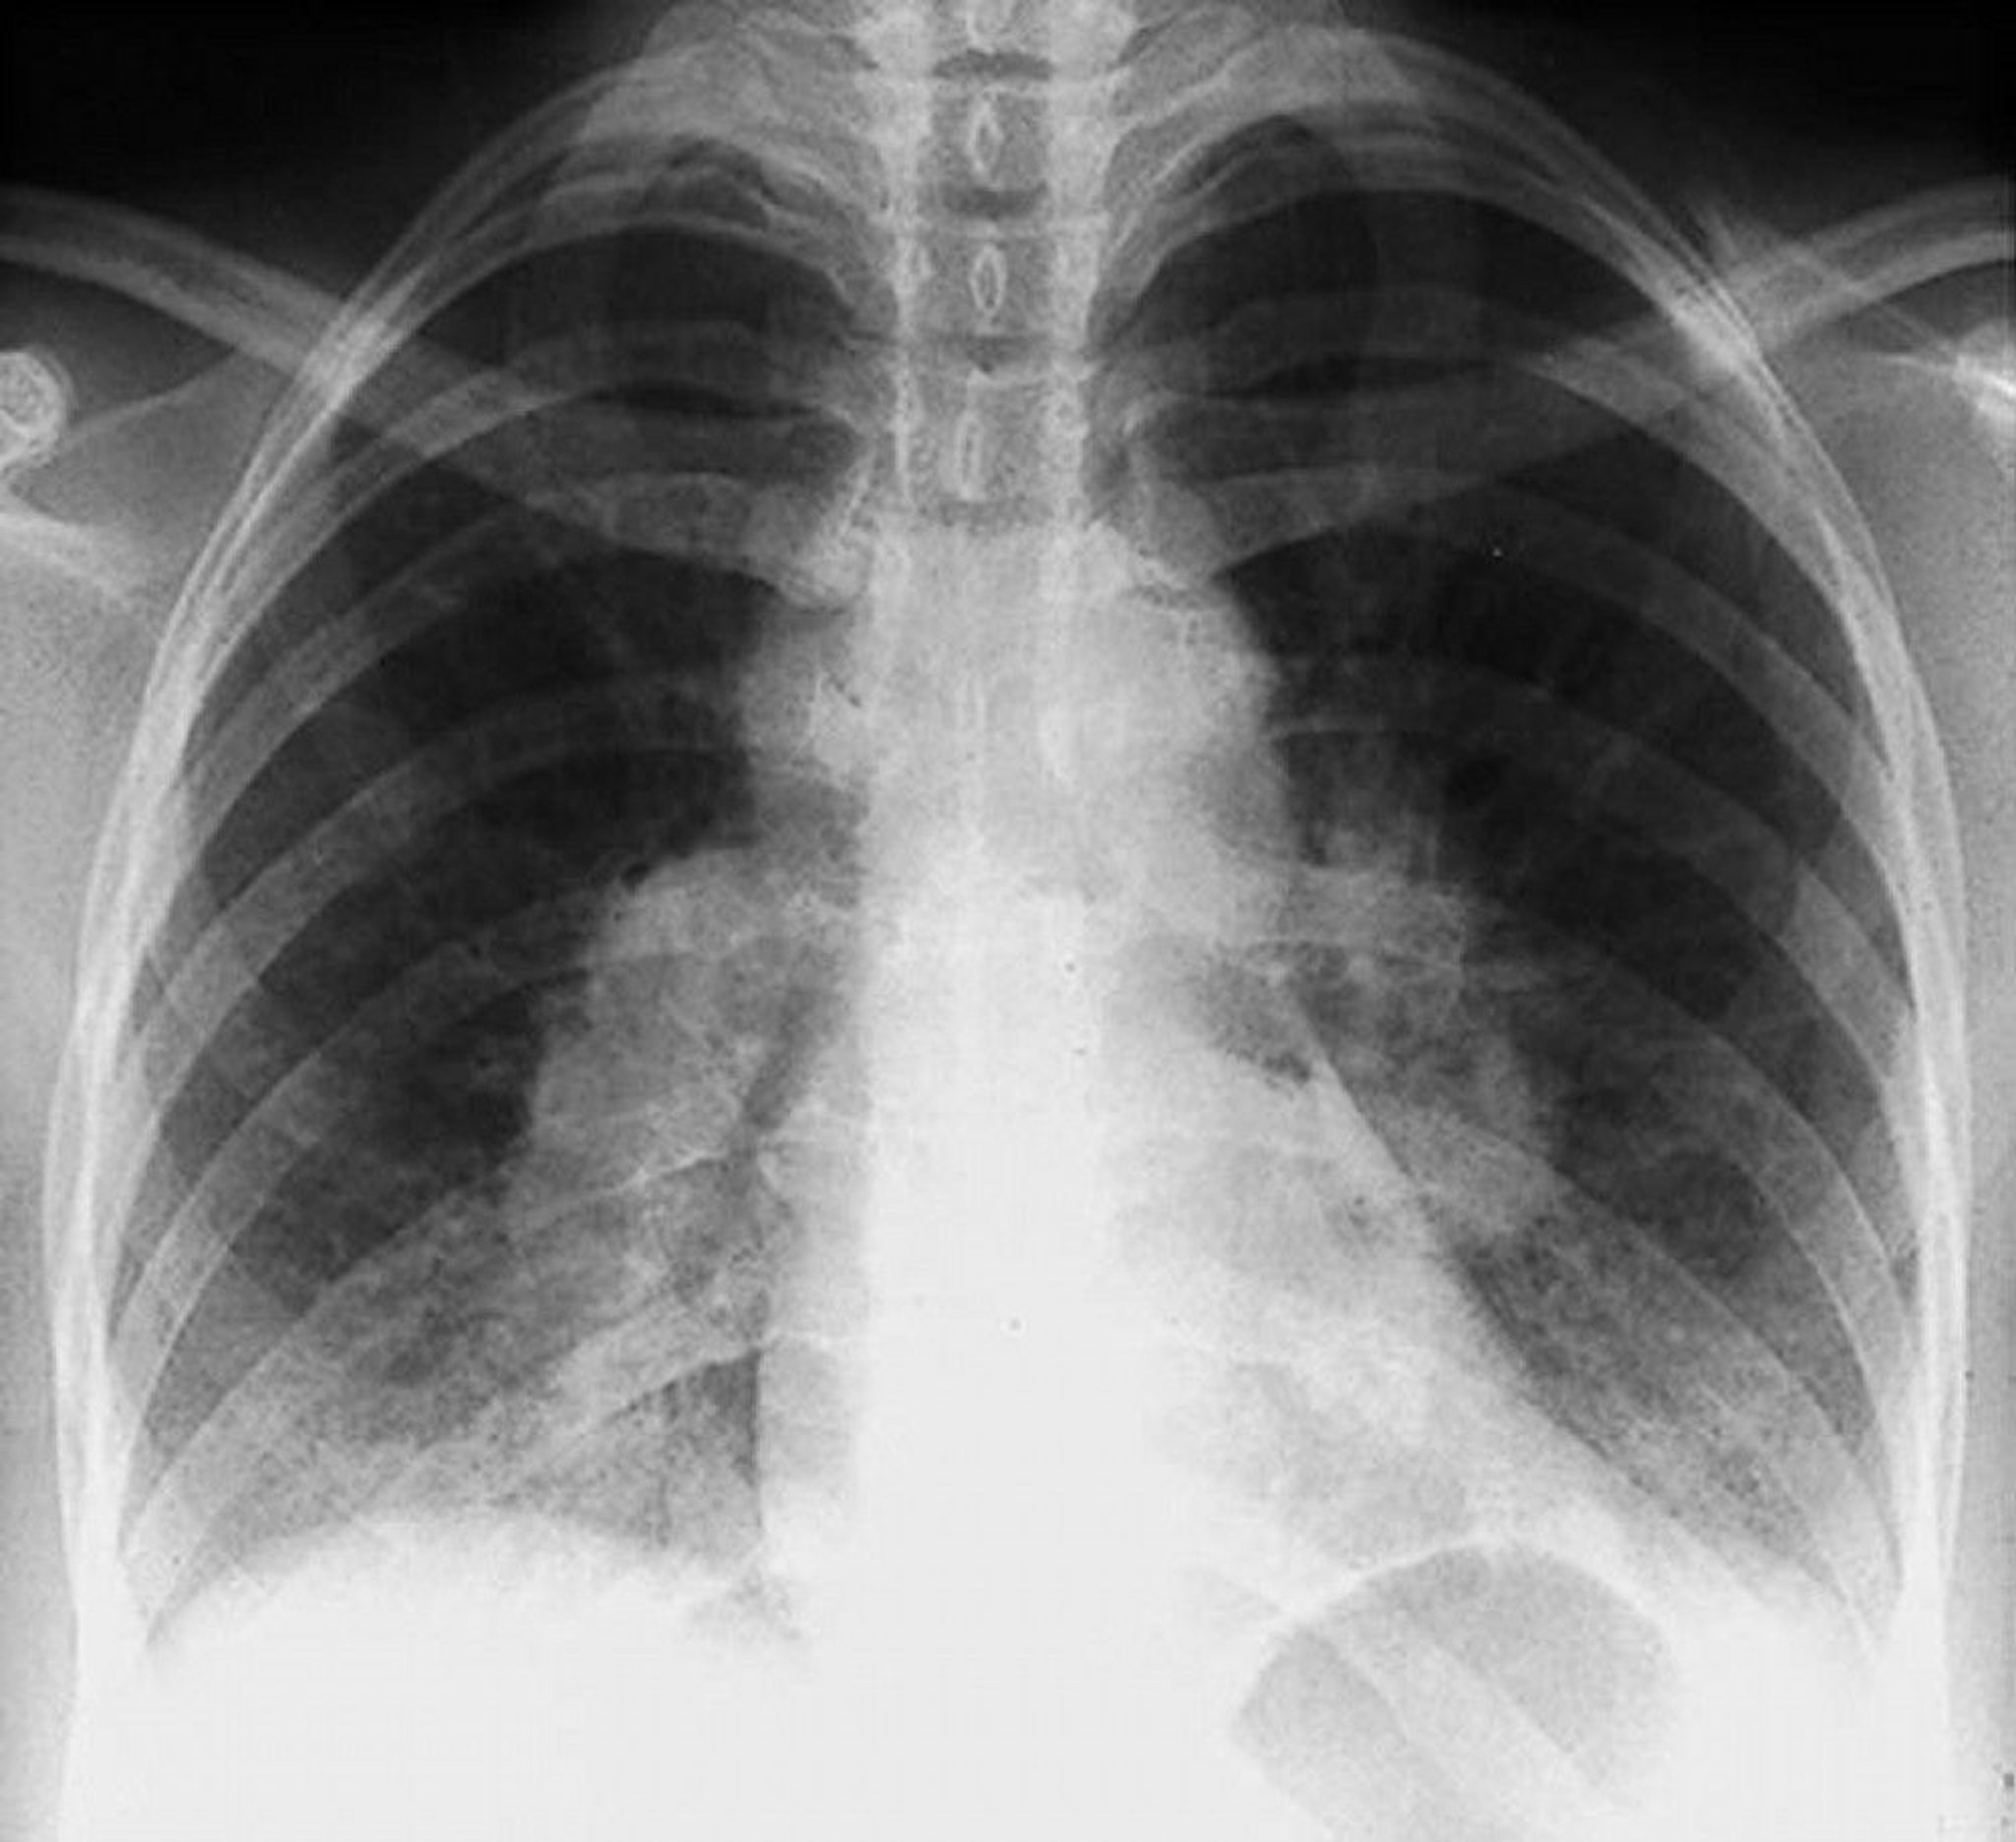

Sarcoidosis (Stage I)

Bilateral hilar adenopathy in stage I sarcoidosis.

By permission of the publisher. From Tanoue L, Elias J. In Bone's Atlas of Pulmonary and Critical Care Medicine. Edited by J Crapo. Philadelphia, Current Medicine, 2005.